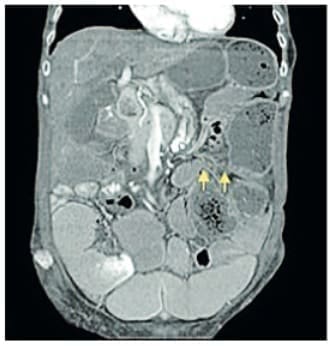

El hemograma no mostraba leucocitosis, la función renal era normal. La radiografía de abdomen simple (Figura 1) mostró una importante dilatación de asas, con niveles hidro aéreos escalonados, presencia de gas distal y materia fecal en recto.

Figura 1. Radiografía de abdomen simple con signos de obstrucción intestinal,

las flechas señalan los niveles hidro aéreos escalonados.

Fuente: archivo de los autores.